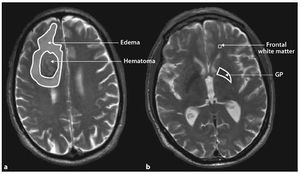

Download scientific diagram| Representative pictures of hematoma and perihematoma edema measurements. a ROIs drawn around the perimeters of the perihematoma edema and hematoma. b ROIs drawn...